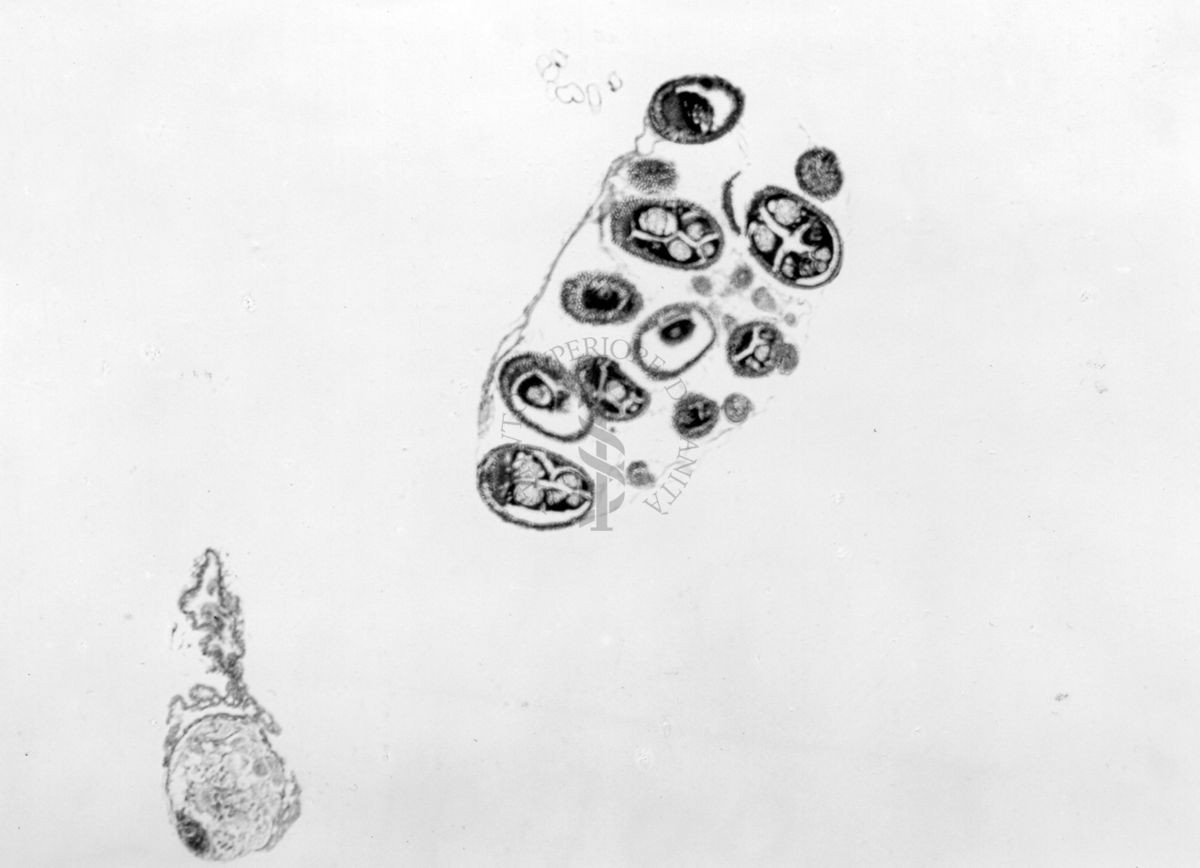

Sezione di un testicolo articolato ad un ovidutto, gonadi con epitelio esterno di sesso opposto ai prodotti sessuali, sezione di 2 gonadi di sesso opposto, immature e articolate a ovidutti

Sezione di un testicolo articolato ad un ovidutto